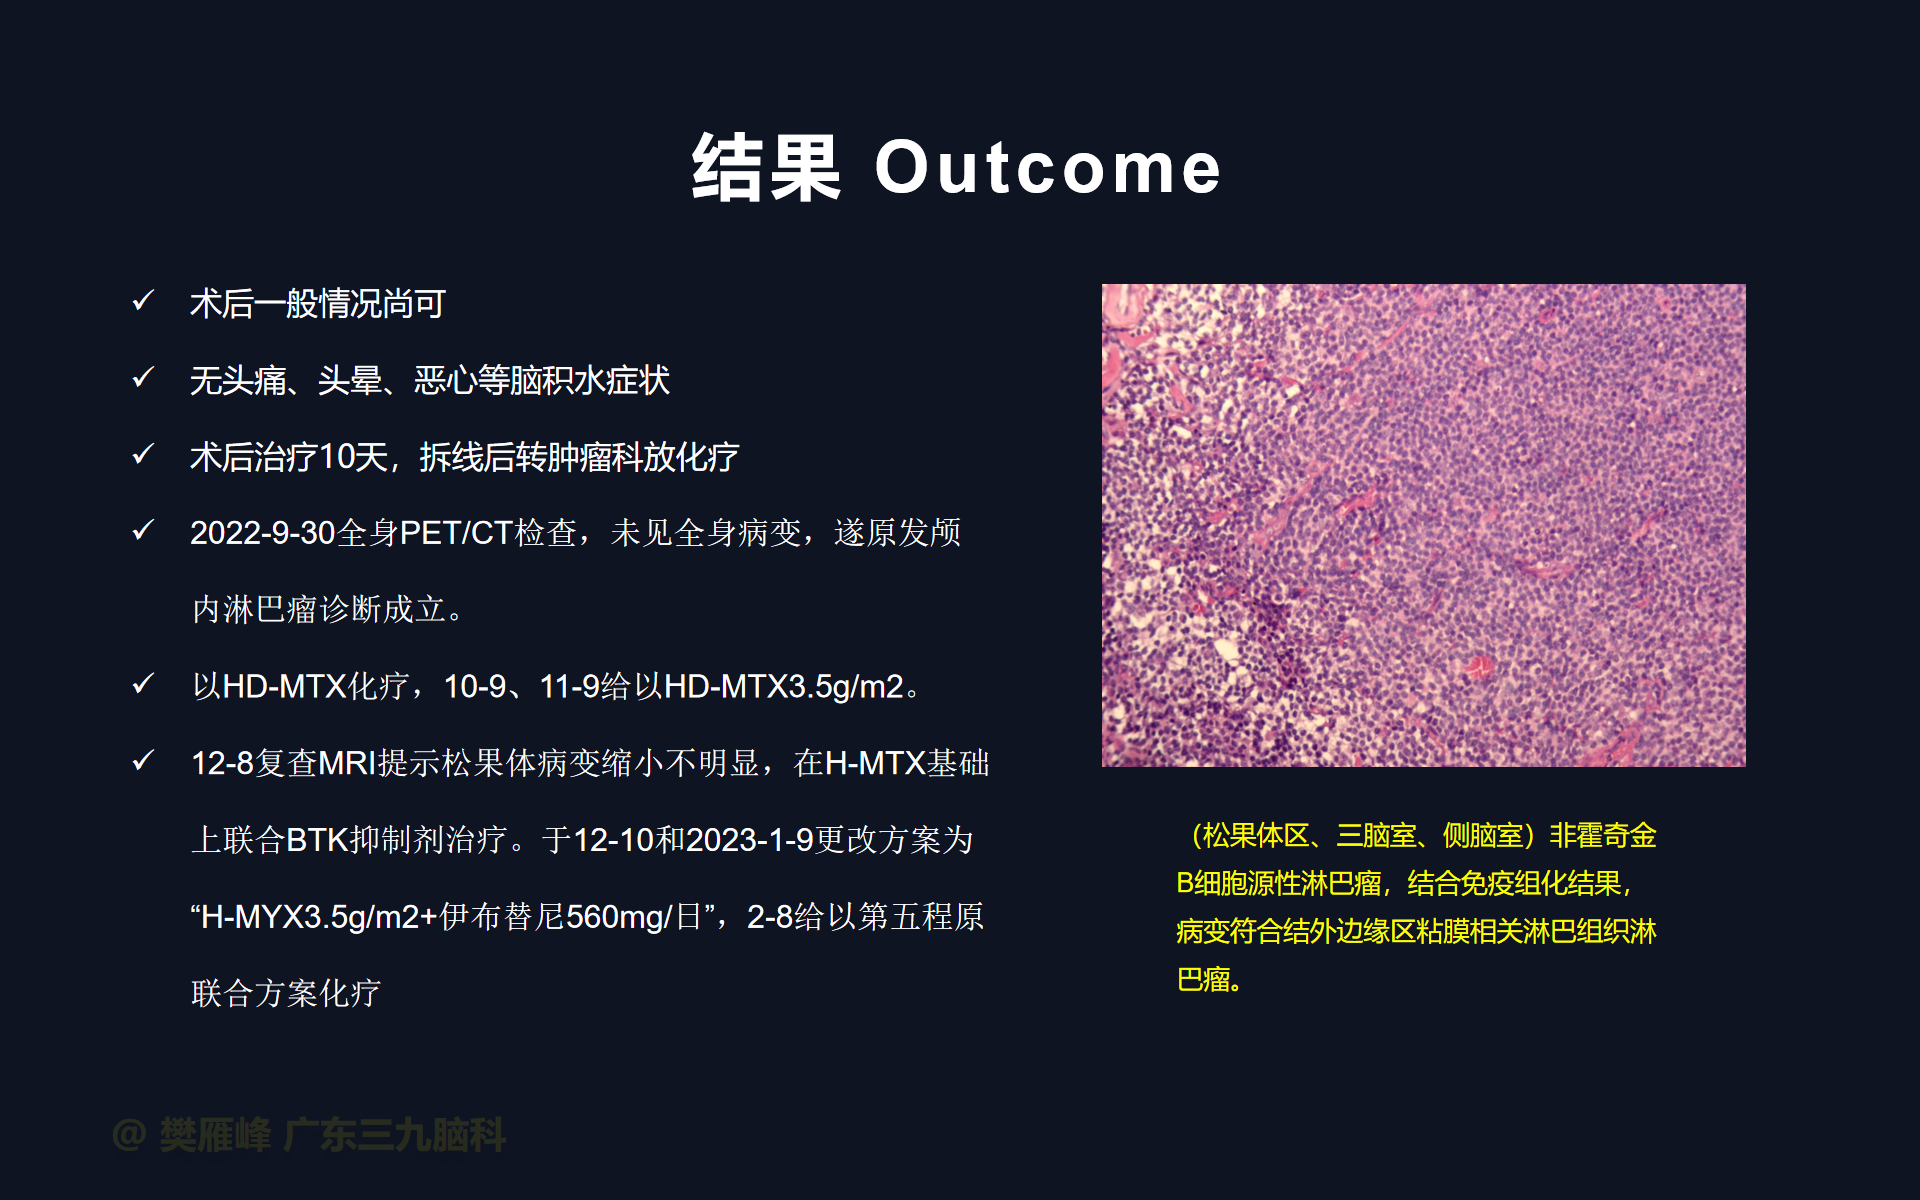

在这个二维手术视频中,展示了2例神经内镜下三脑室底造瘘+活检治疗三脑室后部肿瘤的方法。患者均为三脑室后部病变导致的梗阻性脑积水,病理结果1例为生殖细胞瘤,1例为淋巴瘤,在经过术后的放化疗病情均得到控制,生活质量满意。我们展示了安全的病变活检和第三脑室造瘘的技术要点,以最大限度减少术后继发脑积水和早期并发症。